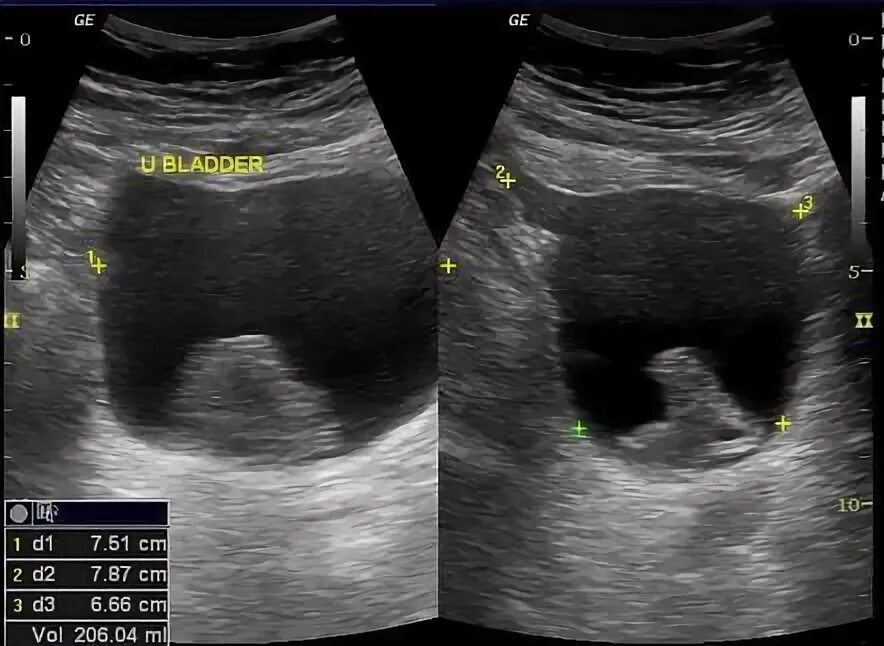

Свободная жидкость в дугласовом пространстве что это